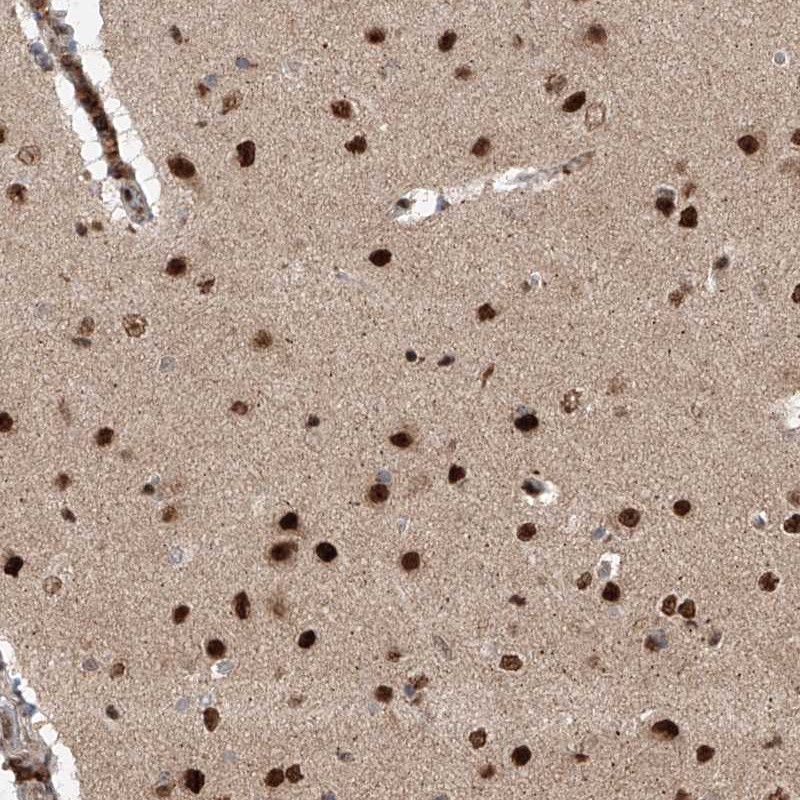

Immunohistochemical staining of human cerebral cortex shows strong nuclear positivity.